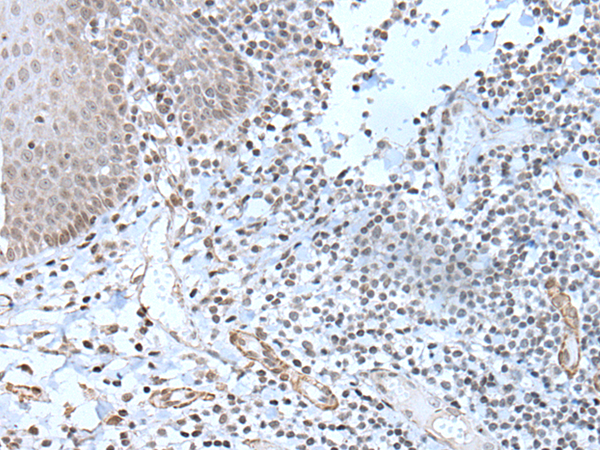

IHC positive control:

Human prostate cancer and human tonsil